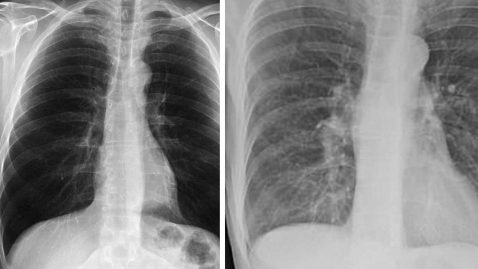

L’Hôpital pour enfants de Toronto a vu débarquer aux urgences, une jeune fille dans un état plutôt alarmant. Elle avait un crayon planté dans la gorge. Elle jouait dans la cour de récréation quand elle a glissé et s’est enfoncée dans le cou, le crayon qu’elle tenait en main. Dans sa malchance, elle a eu beaucoup de chance. En arrivant à l’hôpital, elle ne saignait pratiquement pas, alors qu’elle s’est enfoncée le crayon en plein milieu de la carotide, l’une des plus importantes artères qui irrigue la tête en sang. Comme la plaie ne saignait pas, les médecins ont pris le temps de lui faire un scanner pour mieux comprendre la position exacte de l’objet.

Le crayon a permis d’empêcher le sang de s’écouler et visiblement, la jeune fille, mise à part la douleur, ne souffrait d’aucun autre mal. Les blessures au cou peuvent parfois provoquer des dommages aux voies respiratoires et digestives, et bien entendu au système nerveux. Les chirurgiens ont pu pratiquer l’opération sans difficulté et des antibiotiques ainsi que des fluidifiants sanguins lui ont été prescrits pendant 3 mois. Elle a pu quitter l’hôpital au bout de deux jours. Une visite médicale postérieure a confirmé que la fillette se portait bien et que la plaie guérissait convenablement. Elle devra être suivie, en procédant à d’autres scanners, tous les six mois, puis passera des visites annuelles et enfin, tous les trois ans, elle passera un contrôle afin de suivre l’évolution et d’éviter d’avoir des séquelles.